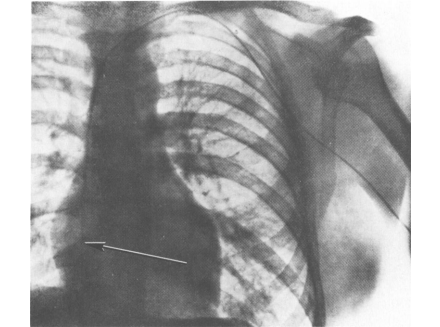

1929 онд Германы мэс засалч Вернер Теодор Отто Форсман өөртөө зүрх цоолох туршилт хийсэн бөгөөд түүний туршилтын үр дүн дэлхий даяар алдартай болжээ. Тэрээр өөртөө хэсэгчилсэн мэдээ алдуулах тархиа хийж, гарынхаа судсаар дамжуулан зүрх рүүгээ зүү хийсэн байна. Гэвч энэ туршилтынх нь дараа түүний ажлаас нь чөлөөлж, бүх насаар нь мэс засал хийх, эмчээр ажиллах эрхийг нь хасжээ. Харин эрдэмтэн Вернер Теодор Отто Форсманд зүрхний катетерын тухайд шинэ нээлт хийсэн хэмээн үзэж 1956 онд Нобелийн шагнал олгосон байна.